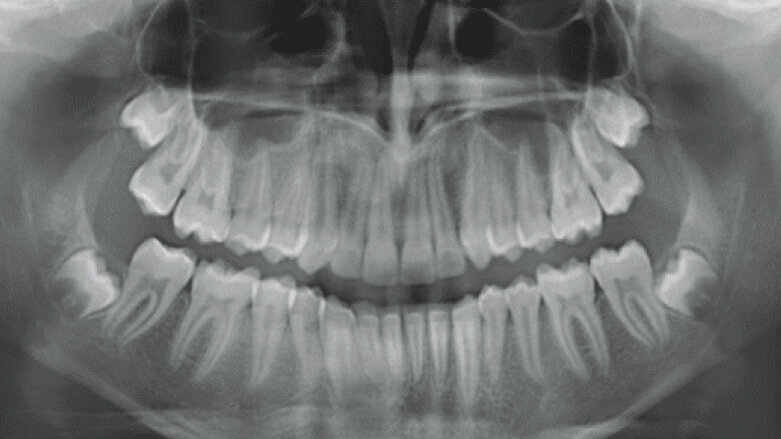

Initial Records

The patient is an 11 year 6 month old male with a chief concern of “overbite.” Diagnostic summary:

Class II, division 1 malocclusion (severe on the right, moderate on the left)

Deep overbite (moderate)

Moderate upper crowding

Mild lower crowding

The slightly retroclined upper incisors and flared lower incisors are consistent with dental compensations for a sagittal jaw discrepancy. The skeletal vertical dimension being within normal limits suggests that the deep bite is predominantly dental in nature.